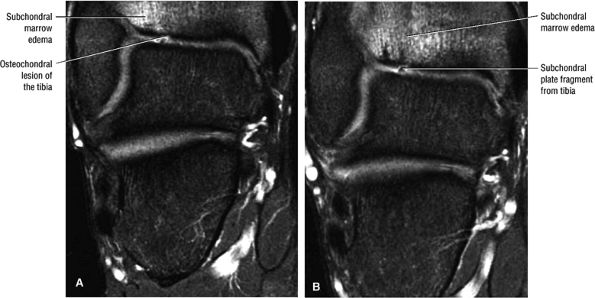

FIGURE 5.102 ● Coronal FS PD FSE images of an osteochondral lesion of the tibia (A). The subchondral plate fragment is defind on a 2-month follow-up study (B).